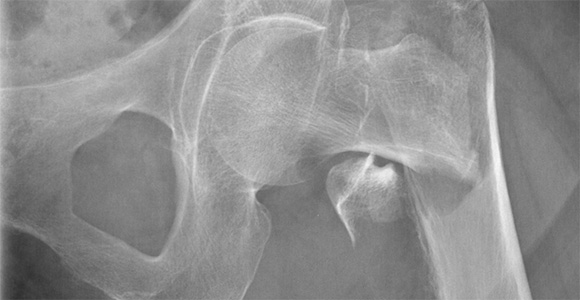

New study: Decline in hip fractures, increase in hip surgeries

Fewer elderly people are experiencing hip fractures, but more are receiving hip replacements due to osteoarthritis.

A new study from the University of Southern Denmark and Copenhagen University Hospital Bispebjerg shows a decline in the frequency of hip fractures among the elderly, but an increase in hip surgeries.

Researchers have discovered a significant decrease in hip fractures among older adults. This positive development is likely due to better treatment of osteoporosis, fall prevention, increased physical activity, and fewer smokers.

While hip fractures have decreased, the number of hip surgeries has increased, especially among the oldest individuals. Improvements in anaesthesia and surgical techniques make it safer to operate on older patients. This reflects a positive trend where modern medical technology helps more elderly people maintain their mobility and quality of life.